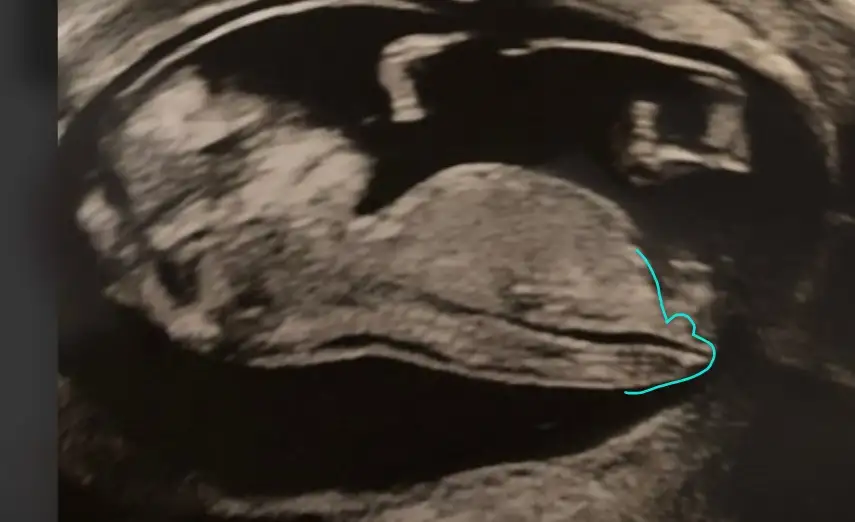

Görünen nub ise Erkek gorunuyorSizce cinsiyeti bellimi 11+5 haftalik:) ben anliyamadim pek

Cok tsk ederimGörünen nub ise Erkek gorunuyorEki Görüntüle 2731396

Olursa tekrar USG paylasinCok tsk ederimKesinlesince yazarim size:)